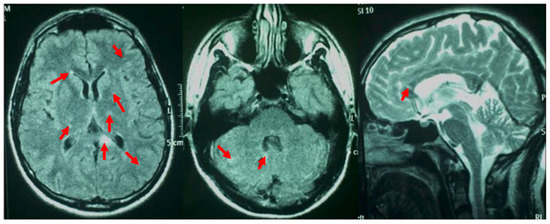

2. Case Report